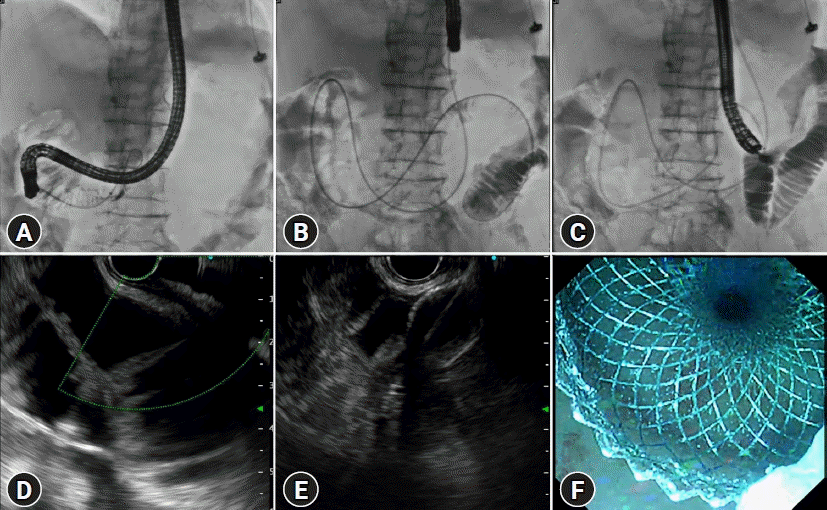

Fig. 3.

Steps of endoscopic ultrasound (EUS)-guided gastroenterostomy using nasobiliary drain assisted technique. (A) A 0.035-inch guidewire is passed into the proximal jejunum guided by large size of retrieval balloon. (B) Under endoscopic and fluoroscopic guidance, a 7-Fr nasobiliary catheter tube is inserted through the guidewire into the proximal jejunum. (C) Saline and contrast media are infused through the nasobiliary drainage tube to inflate the proximal enteric loops. (D) The saline-distended loops of the proximal small bowel are identified by using EUS. (E) EUS-guided puncture and successful deployment of lumen-apposing metal stents (LAMS). (F) The endoscopic view of the deployed LAMS is confirmed by visualizing blue-dyed water (methylene blue) infused through the nasobiliary drain.